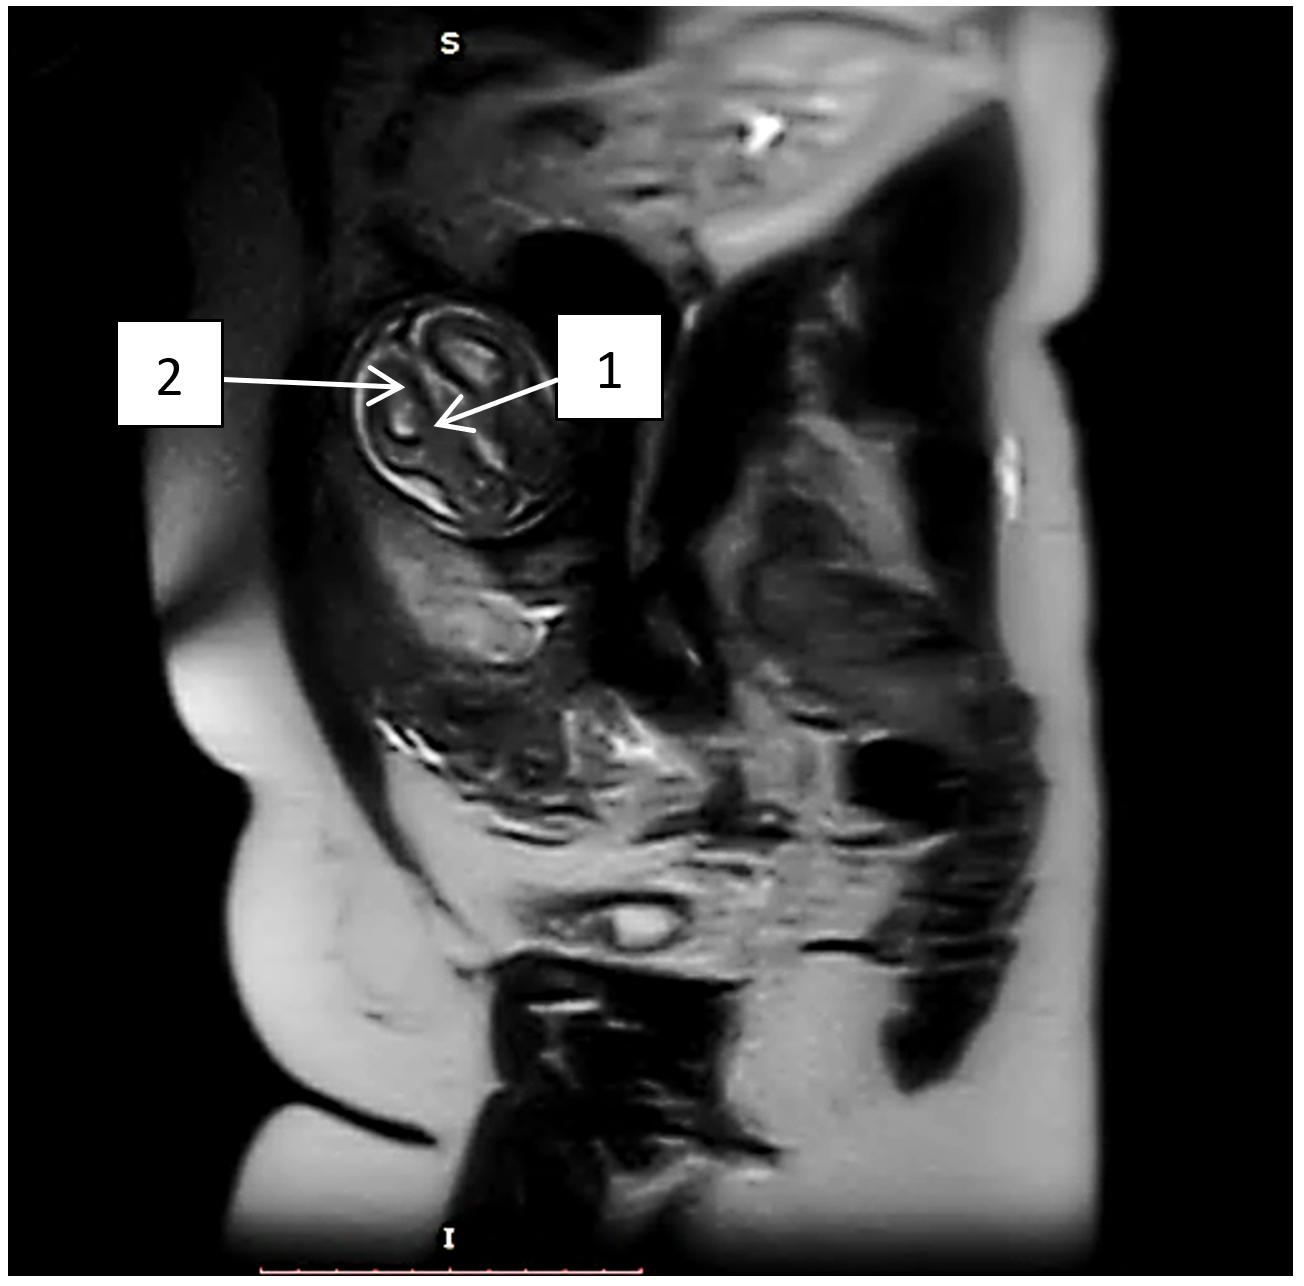

Рисунок 1 - МРТ плода в сагиттальной проекции Т2 ВИ:

1 - агенезия мозолистого тела; 2 - расширение межполушарной щели